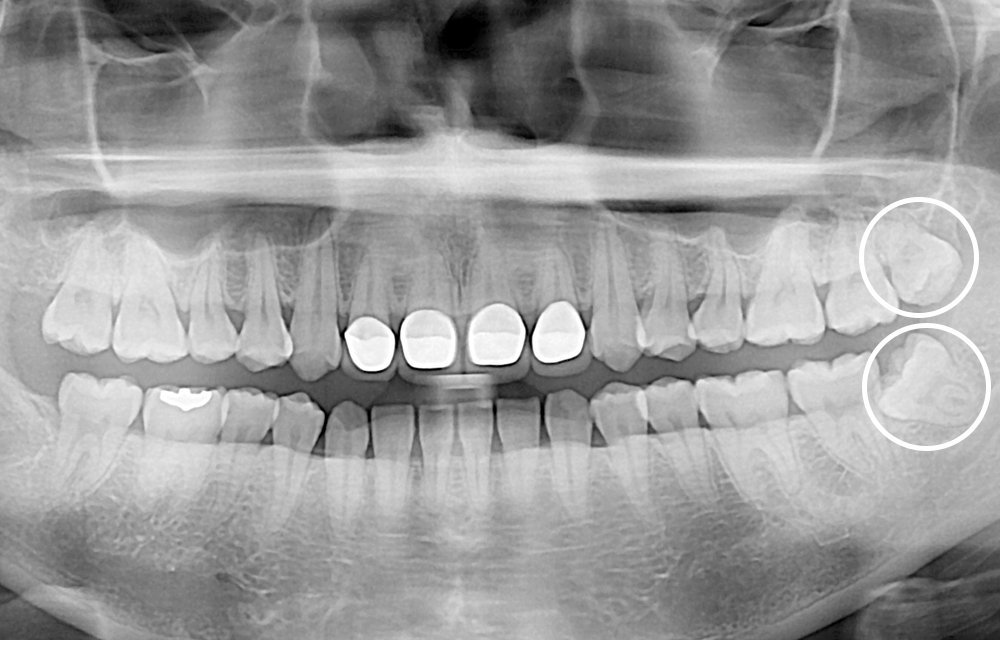

[사랑니] 매복 사랑니 발치

치료전 : 2020-02-17

세종치과는 구강악안면외과학 박사이신 원장님이 발치하는 치과입니다.